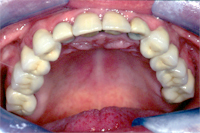

Im Röntgenbild von Abb. 3 ist ein gut erbsengrosses Granulom (Pfeil) an der Wurzelspitze eines toten, devitalen Zahnes feststellbar. Die Patientin wünschte die Erhaltung des Zahnes, zumal auch der vordere Nachbarzahn marktot und beherdet war. Abb. 4 zeigt das Röntgenbild nach der Wurzelfüllung.

Ein halbes Jahr später hat die Patientin sich dazu entschlossen, den vorderen beherdeten Zahn auch endodontisch behandeln zu lassen. An Abb. 5 wird im Röntgenbild die Wurzellänge mit Instrumenten bestimmt. Man gewinnt auch den Eindruck, dass der bereits vor einem halben Jahr wurzelbehandelte Zahn in Abheilung sei.